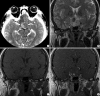

We report a case of pituitary apoplexy resulting in right internal carotid artery occlusion accompanied by hemiplegia and lethargy. A 43-yr-old man presented with a sudden onset of severe headache, visual disturbance and left hemiplegia. Investigations revealed a nodular mass, located in the sella and suprasellar portion and accompanied by compression of the optic chiasm. The mass compressed the bilateral cavernous sinuses, resulting in the obliteration of the cavernous portion of the right internal carotid artery. A border zone infarct in the right fronto-parietal region was found. Transsphenoidal tumor decompression following conservative therapy with fluid replacement and steroids was performed. Pathological examination revealed an almost completely infarcted pituitary adenoma. The patient's vision improved immediately after the decompression, and the motor weakness improved to grade IV(+) within six months after the operation. Pituitary apoplexy resulting in internal carotid artery occlusion is rare. However, clinicians should be aware of the possibility and the appropriate management of such an occurrence.